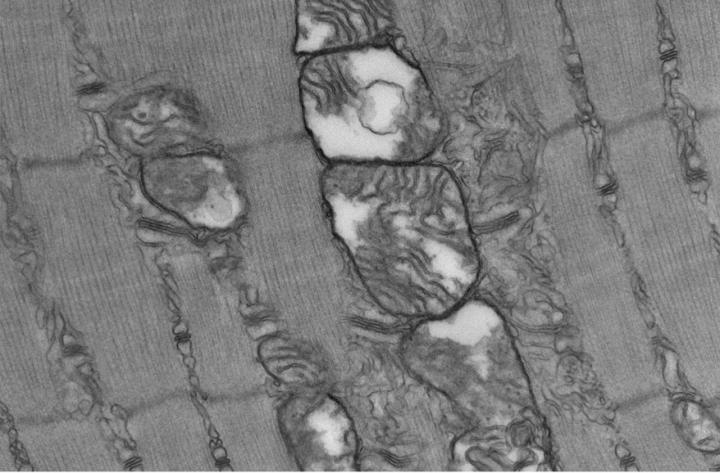

image: Sepsis triggers profound long-lasting ultrastructural defects in skeletal muscle mitochondria.

Instead, they discovered that energy-producing mitochondria in the animals' muscle cells were abnormal and showed signs of ongoing oxidative damage. "This suggests that chronic muscle weakness among sepsis survivors is not due to muscle wasting, but rather caused by the loss of muscle quality," Owen says.